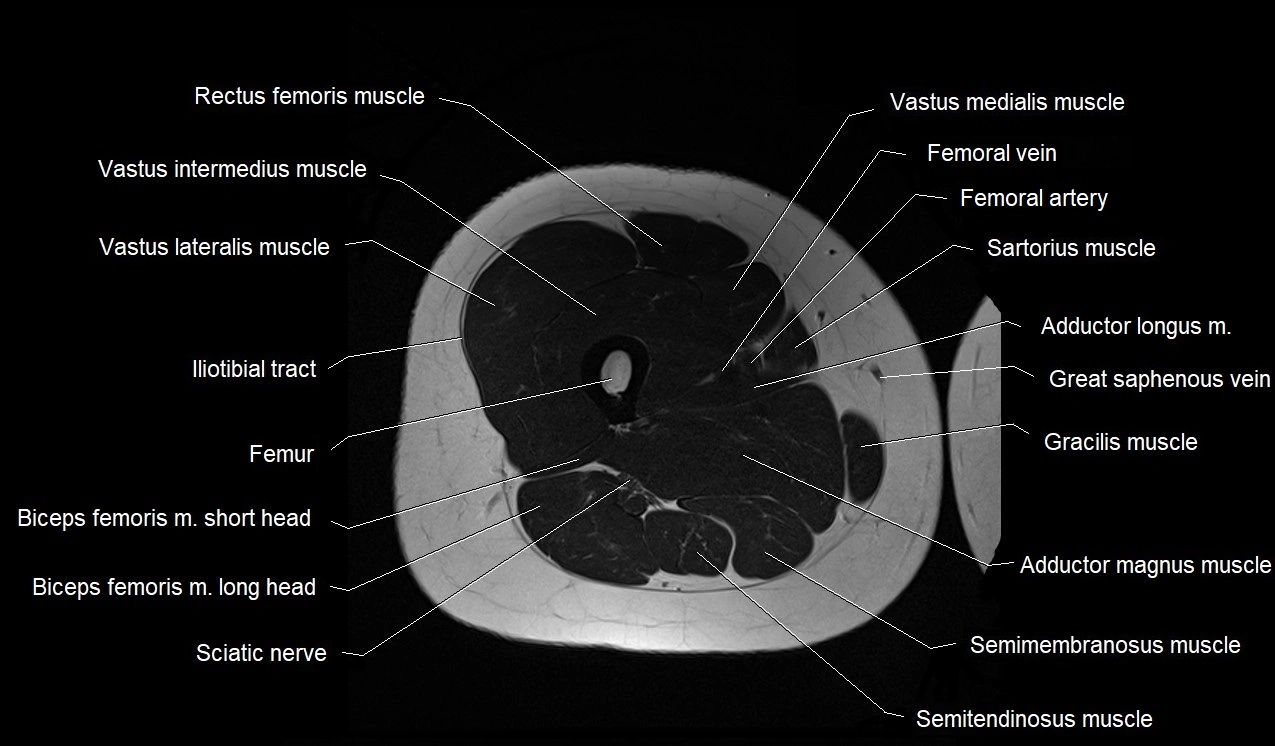

- Biceps femoris muscle (Long head)

- Biceps femoris muscle (Short head)

- Femoral artery

- Femoral vein

- Femur

- Gracilis muscle

- Iliotibial tract

- Rectus femoris muscle

- Sartorius muscle

- Semimembranosus muscle

- Semitendinosus muscle

- Tibial nerve

- Vastus intermedius muscle

- Vastus lateralis muscle

- Vastus medialis muscle

- great saphenous vein